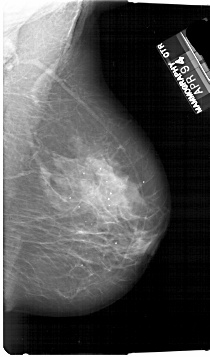

A_1728_1.RIGHT_MLO

RIGHT_MLO LINES 6781 PIXELS_PER_LINE 3976 BITS_PER_PIXEL 12 RESOLUTION 43.5 NON_OVERLAY